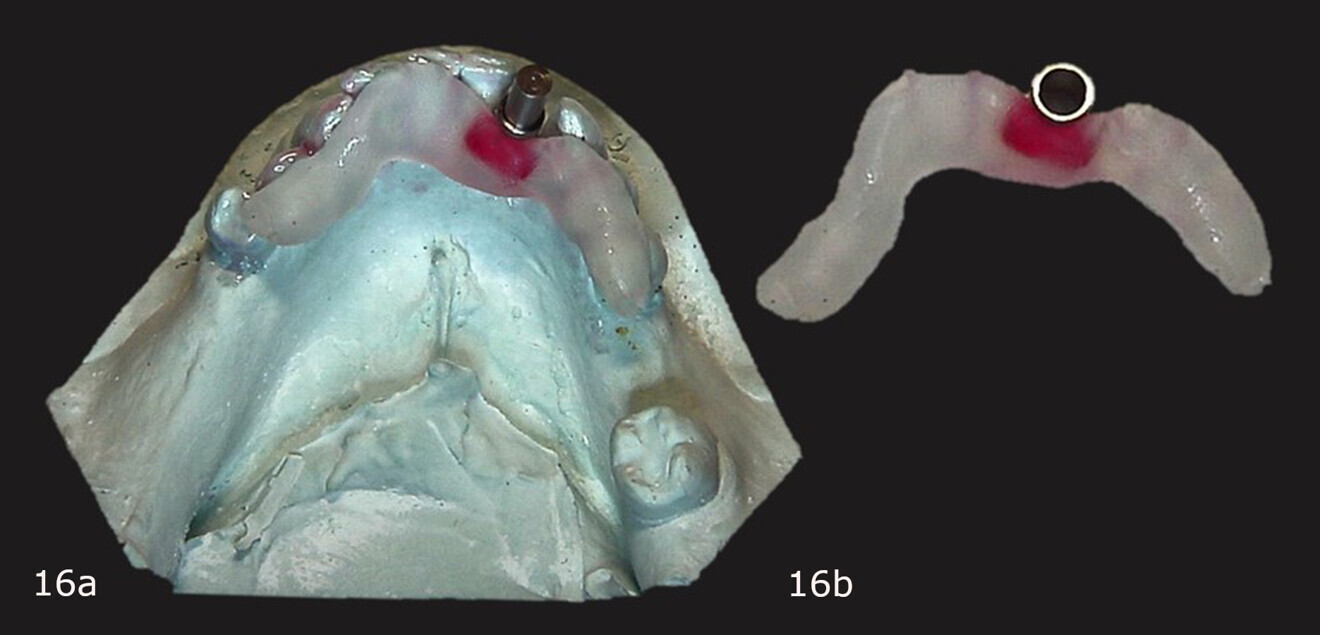

Figs. 16a & b: Primopattern LC Gel placed over the cleat and primosplint adapted to the cast (a). Corrected surgical guide after light polymerisation (b).